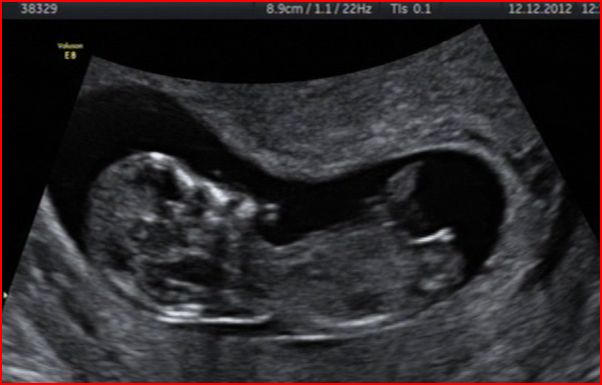

I have attached a copy of some stills from the dvd we have been given if anyone fancies a guess at the nub - first proper shot of baby is (by the us clock) ironically at 12:12 on the 12.12.2012.

Baby was 12+1 at the time of shots (hopefully, if everthing is ok and i haven't m/c'd before then from the cvs, i will post another one that i get from my 13 week nt scan on tuesday)